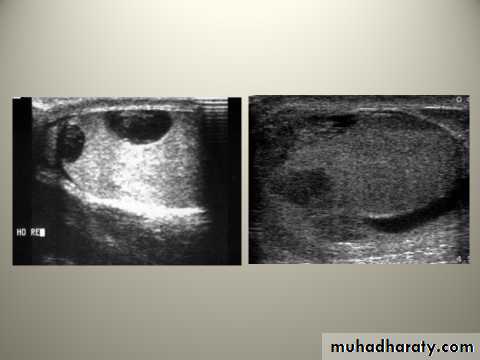

Blunt or penetrating traumaContusion and rupture of the testis are associated with a collection of blood around the testis and cannot usually be distinguished with certainty without exploration.

O/E: scrotal swelling, bruises, Loss of testicular contour

U/S is the investigation of choice

Haematocele ( collection of blood between two layers of tunica vaginalis) should be drained and the tunica albuginea repaired after evacuation of haematoma.